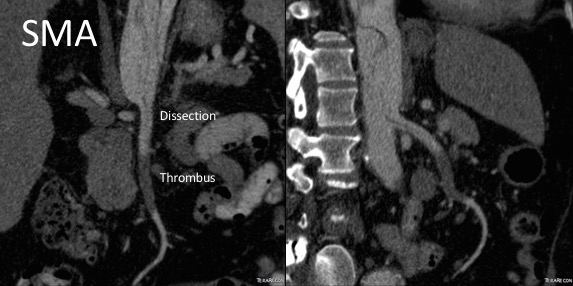

In this patient, thrombosis occured in the SMA beyond the origin due to dissection and decreased flow. This was consistent with the patient’s complaint of generalized abdominal pain and examination findings of pain out of proportion to the exam, indicating acute mesenteric ischemia.

His laboratory findings were within normal ranges, indicating this was early in the process. It is important to remember that no lab value correlates with acute mesenteric ischemia except very late in the process, and acute mesenteric ischemia remains a clinical diagnosis (reference 1) that is associated with a high mortality rate.